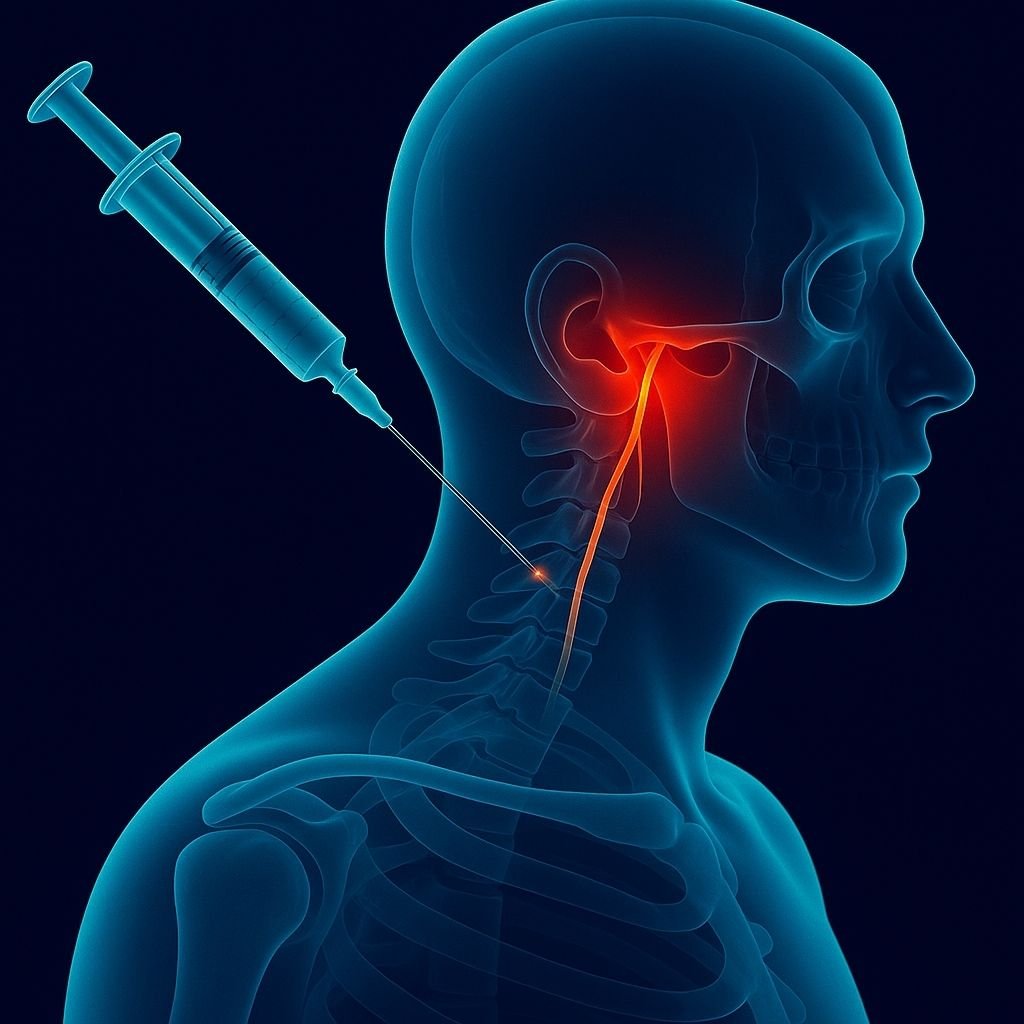

Hasta yüzüstü yatırılır.

Floroskopi (X-ray) cihazı ile ilgili omurga seviyesi görüntülenir.

İnce bir iğne, sinir kökünün çıktığı foramene yönlendirilir.

İğnenin doğru yerde olduğu kontrast madde ile teyit edilir.

Steroid ve lokal anestezik ilaç, sinirin etrafına enjekte edilir.

İşlem ortalama 20 dakika sürer, hasta kısa sürede ayağa kalkabilir.